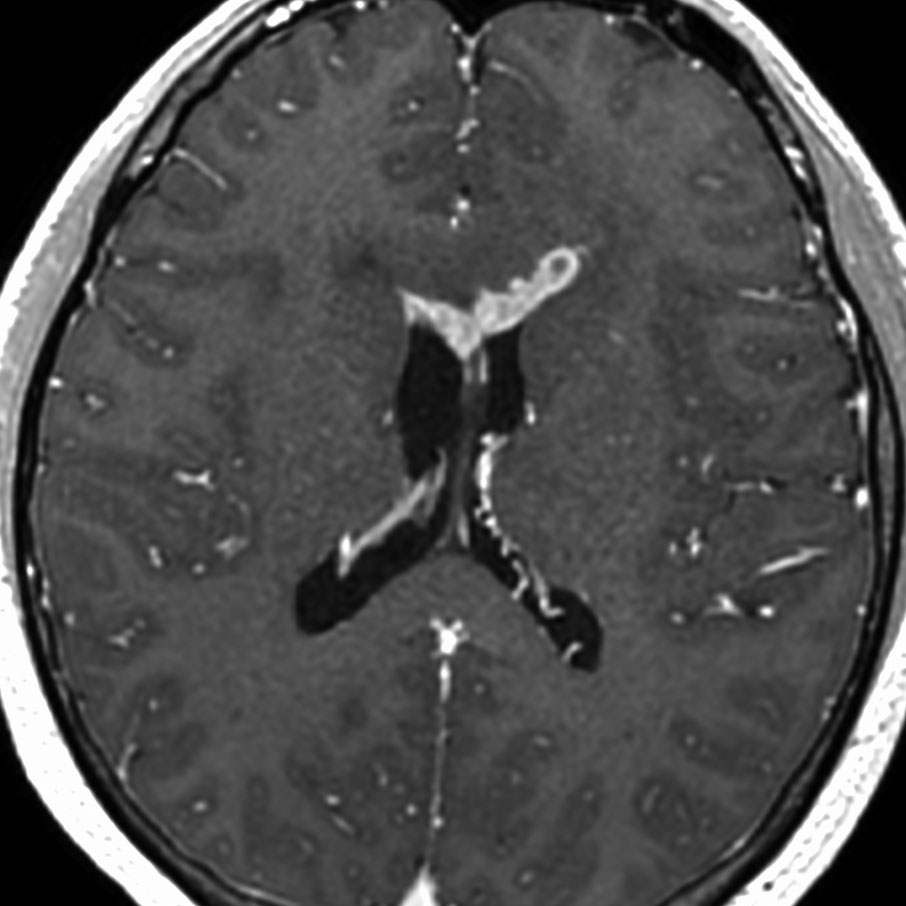

ガドリニウム増強では,前頭葉腫瘍というより,側脳室壁にベトベトくっついているような腫瘍です。germinoma特有のsubependymal infiltration像を示します。

左はICE化学療法 (IFO/CDDP/VP-16)前,右は1コース終了後です。腫瘍は顕著に縮小してgerminomaとして普通の化学療法反応性を示します。また,松果体と下垂体には腫瘍はありません。